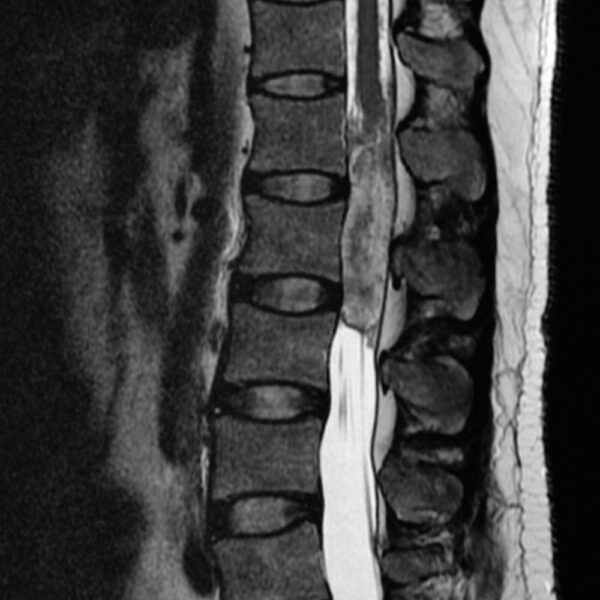

MRI

Showing 1–9 of 86 results